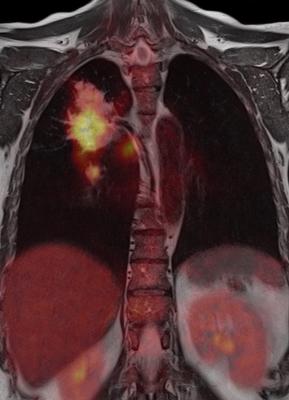

Moreover, on different systems, metabolic and structural images have to be acquired independently, requiring sequential patient examination and read-by-side, which makes the process error-prone. It became obvious that combining imaging modalities was the next step in advancing imaging technology. CT/PET imaging modality was one of the initial steps in that direction, combining the high speed of acquisition and high spatial resolution achieved with CT with high sensitivity and functional metabolic imaging capabilities achieved with PET.

MRI has several advantages over CT, especially for use in clinical trials. These include the absence of ionizing radiation, which makes the modality safe for serial longitudinal imaging, accurate anatomical localization, good soft tissue contrast and the ability to image in multiple planes in a single setting. It is expected that clinical trials in the oncology, neurology and cardiovascular therapeutic areas will benefit the most from this hybrid technology.

In oncology, the MRI component has proven beneficial for malignant diseases such as brain, breast, bone and head and neck tumors. In particular, MRI is the preferred modality for liver metastatic lesions because of its ability to detect small liver parenchymal lesions. Combining this technology with PET significantly enhances the sensitivity of detection of liver lesions and improves characterization of liver pathology. In a study published in the Nature medicine journal1, the authors reported success by demonstrating early detection of soft tissue tumors in a preclinical model, thereby paving way for an early therapeutic intervention using the hybrid technology.

MRI/PET hybrid scanners offer application to molecular imaging, which involves targeting individual receptors with radioligands, making them visible on PET and overlaying that information on high-resolution MR images for anatomical localization. Diffusion weighted imaging (DWI) offers special insight into diffusion changes in tissue resulting from ischemic disease and response to therapy, for example, in neuroendocrine tumors where PET provides hormone receptor expression information, complementing diffusion information from MRI.